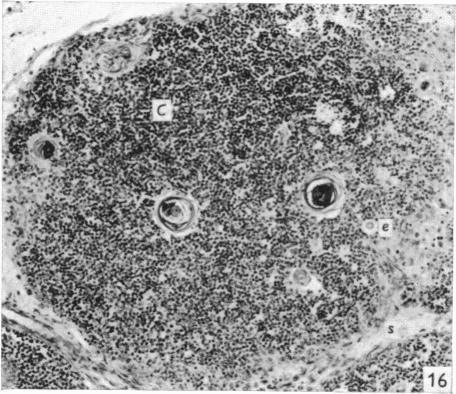

The effect of castration, oestrogens, testosterone and the oestrous cycle on the cortical epithelium of the thymus in male and female rats.

J Anat. 1968 Jun;103(Pt 1):113-33.